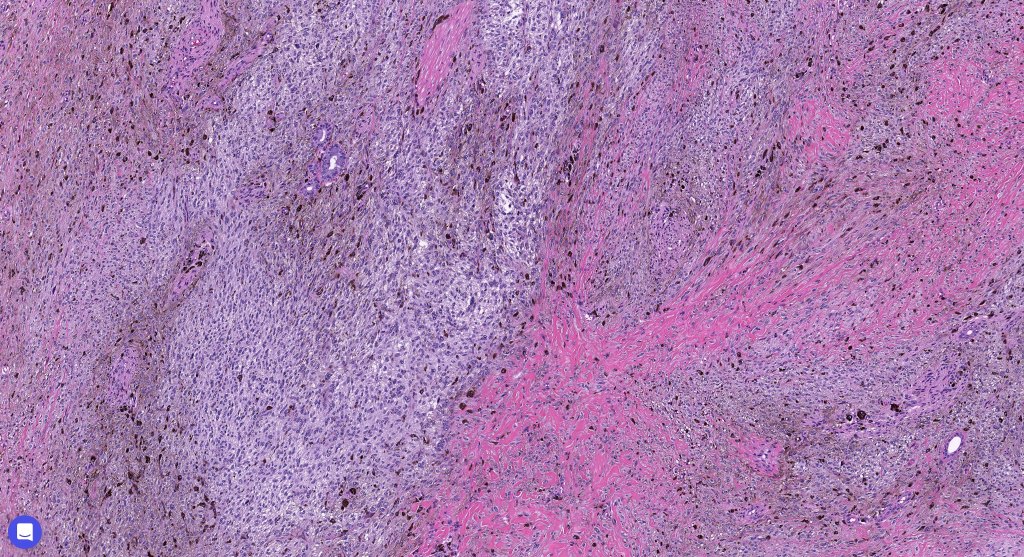

•Admixture of spindle cells, pigmented bipolar or dendritic cells & melanophages

•Cytoplasm is pale and nuclei are small with inconspicuous nucleoli

•An alveolar pattern is characteristic particularly with clear cell nodules

•Mitoses are typically very sparse or absent

•No atypical mitoses

•Multinucleate giant cells sometimes present

•Some tumors are composed spindle cells in a fascicular or neuronevoid pattern